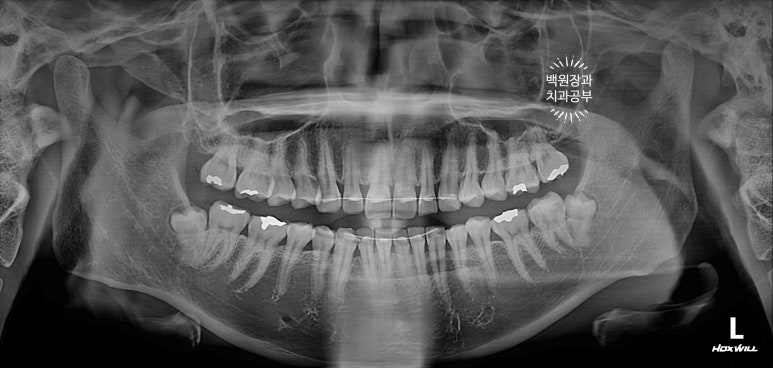

치과용 파노라마 엑스레이를 보시면, 아마도.. 기존의 교정 유지장치 때문에 옆면 cleansing이 어렵게 되어 충치가 생겼음을 예상해볼 수 있습니다.

노란색 원으로 표시해둔 곳은 앞니 옆면 (인접면) 충치이고, 빨간색 원으로 표시해둔 곳은 기존 레진충전의 변색입니다.